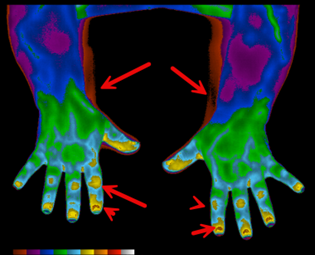

Spectron IR Medical Infrared Images